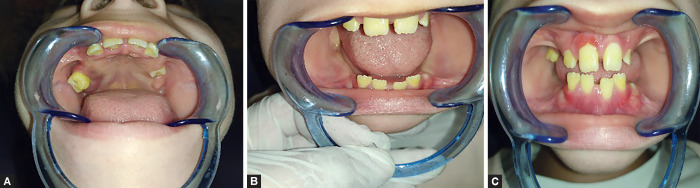

Papillon-Lefèvre syndrome (PLS), also known as keratosis palmoplantaris with periodontopathia and "hyperkeratosis palmoplantaris with periodontosis," is a rare autosomal recessive disorder, characterized by diffuse palmoplantar keratoderma and precocious aggressive periodontitis, leading to premature loss of deciduous and permanent dentition at a very young age. The aim of this article is to revisit PLS, address its diagnosis update and dental management, and to provide insight into the fascinating role of consanguinity in the etiology of this unusual illness. We report the case of two Moroccan sisters aged 5 and 8 years old with PLS who consulted the pedodontics department at the CCTD in Rabat, Morocco, for the early loss of teeth.